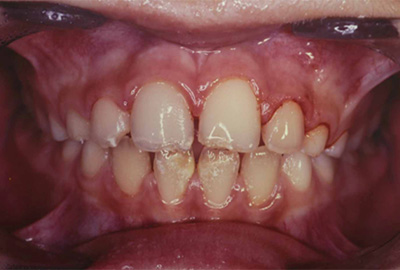

CASO CLÍNICO Paciente de diez años que acude a consulta de urgencias por haber sufrido un accidente deportivo 72 horas antes y como consecuencia del cual presentaba avulsión del incisivo central superior izquierdo 2.1.La familia guardó el incisivo en el congelador doméstico y acudió en esta situación a la clínica dental, pasadas 72 horas desde el traumatismo. Se exploró al paciente no apreciando fracturas óseas ni de otros dientes (Figura 1), se evaluó el diente avulsionado no apreciando fractura radicular ni coronal (Figura 2). Se exploró la zona alveolar no apreciando fracturas en las paredes del hueso alveolar. Después de obtener datos en la exploración clínica y debido a la edad del paciente se decidió realizarel reimplante.Tras la anestesia infiltrativa con lidocaina sin vasoconstrictor, selavó el diente avulsionado con suero fisiológico y se comprobó la adaptación del diente al alveolo.Se realizó el tratamiento de conductos en mano(Figura 3),y se eliminó el tejido pulparnecrótico y la posible contaminación bacteriana del mismo. La preparación quimio-mecánica se realizó con técnica manual, irrigando el conducto con hipoclorito sódico al 5% después de cada lima instrumentando hasta el número 30 con latécnica de step-bachy obturando con gutapercha y cemento Sealapex® (Kerr/Sybron, Romulus, MI EEUU).Posteriormente se realizó el reimplante del diente en el alveolo y la ferulización con alambre de ortodoncia y adherido con composite (Figura4).Se realizó una radiografía periapical de control (Figura5); citando al paciente para control en una semana. A las tres semanas se retiró la ferulización(Figura 6) y se realizó otra radiografía periapical (Figura7).Se realizaron controles clínicos al mes y seis meses, en los que no se apreció cambios en la evolución clínica. Tres años después a la exploración se apreció asimetría incisal atribuible a la detención dela erupción del 2.1, con limitación del crecimiento vertical(Figura8). Se observó los bordes incisales a distinta altura de los dientes 1.1 y 2.1, que son consecuencia de la anquilosis dental del 2.1 por lo que se aconsejóla erupción ortodóntica del 2.1 pero que el paciente no aceptó.El paciente permaneció sin síntomas inflamatorios. Diez años después de realizado el reimplante la radiografía periapical(Figura 9), muestra la reabsorción por sustitución y anquilosis dental como evolución del reimplante.En la exploración clínica el 2.1 presenta un retraso en la erupción, por la falta de crecimiento óseo vertical, con la consiguiente inclinación mesial del 1.1. El 2.1 presenta una restauración estética del borde incisal que fue realizada a los siete años del reimplantepara intentar mejorar la estética del paciente.A los quince años la radiografía periapical del reimplante (Figura 10), no muestra signos de inflamación activa, pero se puede observar la pérdida del contorno radicular en la zona media de la raíz en la cara distal; lo que indicaría la reabsorción radicular con aposición ósea posterior. DISCUSIÓN La educación de la población ante traumatismos dentales juega un papel muy importante a la hora de actuar en el lugar del accidente, especialmente en avulsiones dentales , lo que mejoraría el pronóstico de estos traumatismos. El tratamiento de un paciente que ha sufrido avulsión dental es largo y suele requerir un tratamiento multidisciplinario por lo que la colaboración del paciente y su familia es imprescindible , .En un reimplante tardío la evolución hacia la anquilosis es muy frecuente, siendo el factor más importante el tiempo en que el diente ha permanecido seco . En pacientes en crecimiento,la anquilosis, conlleva la falta de desarrollo óseo en sentido vertical, por lo queFillippi y cols. proponen que ante los primeros signos de anquilosis debemos recolocar el diente y recubrirlo con Emdogain, presentando algunos casos con buenos resultados en los que la anquilosis se detuvo. Tropeycols(6)aconsejan la sección de la corona y su extracción en los casos en los que aparezca anquilosis e infraoclusión de 2mm, dejando la raíz enterrada en el hueso para ser sustituida por éste y así poder favorecer el crecimiento vertical y posibilitar un mejor resultado estético definitivo.Ante la presencia de anquilosis en pacientes en crecimiento debemos actuar y no dejar el caso a su evolución natural puesto que el problema final será de más difícil solución(6). Es importante tener en cuenta que el autotransplante, generalmente con premolares, es una opción terapéutica de resultados predecibles , especialmente en pacientes en crecimiento que han perdido hueso y/o dientes en los que el reimplante no se pueda realizar o bien no vaya a tener resultados exitosos. El autotransplante mantiene el espacio dental, remodela el hueso alveolar y favorece el crecimiento óseo(10), por lo que funcional y estéticamentese puede obtener un resultado predecible. La sustitución de dientes perdidos por avulsión dental suele realizarse mediante la colocación de implantes dentales , lo que implica mantener al paciente durante varios años con soluciones provisionales hasta obtener el crecimiento definitivo del maxilar , alrededor de los 20 años de edad. En ocasiones a pesar de haber realizado tratamientos multidisciplinariosparamantener el espacio y los tejidos óseos y mucosos del diente perdido, a la hora de realizar el tratamiento definitivo con implantes dentales, no se puede obtener un buen contorno alveolar y altura ósea , ,lo que ocasiona un problema estético de difícil tratamiento. CONCLUSIÓN La avulsión dental tiene como consecuencia la probabilidad de la no supervivencia o la pérdida del ligamento periodontal. El paciente que está en crecimiento el pronóstico es desfavorable dado que las complicaciones son frecuentes. Se justifica el reimplante del caso por la edad del paciente y para posponer decisiones a una edad adulta. En el caso aquí presentado dada la evolución favorable no fue necesario el implante dental en el control realizado a los 15 años. La infraoclusiónpor anquilosis del diente reimplantado,se solucionó con restauración estética. BIBLIOGRAFÍA Bastone EB, Freer TJ, McNamara JR. Epidemiology of dental trauma: a review of the literature. Aust Dent J. 2000;45:2-9. Wriedt S, Martin M, Al-Nawas B, Wehrbein H. Long-term effects of traumatic injuries to incisors and periodontal tissuesduring childhood. J OrofacOrthop. 2010;71:318-29. Flores MT, Andersson L, Andreasen JO, Bakland LK, MalmgrenB, Barnett F et al. Guidelines for the management of traumatic dental injuries. II. Avulsions of permanent teeth.Dent Traumatol. 2007;23:130-6. .Andersson L, AndreasenJ O, Day P, Heithersay G, Trope M, Diangelis AJ, Kenny DJ, Sigurdsson A, Bourguignon C, Flores MT, Hicks ML, Lenzi AR, Malmgren B, MouleAJ,Tsukiboshi M. International Association of Dental Traumatology guidelines for the management of traumatic dental injuries: 2. Avulsion of permanent teeth.Dent Traumatol. 2012; 28: 88-96. Trope M. Avulsion of permanent teeth: theory to practice. Dent Traumatol. 2011;27:281-94. Hecova H, Tzigkounakis V, Merglova V, Netolicky J. A retrospective study of 889 injured permanent teeth. Dent Traumatol. 2010;26:466-75. MonaAl-Sane, Bourisly N,TaghreedAlmulla, Andersson L. Laypeoples preferred sources of healthinformation on the emergency management of tooth avulsión.Dent Traumatol. 2011; 27: 432-7. Maseng AL,Skaare AB. Management of a 9-year-old boy experiencing severe dental injury - a 21- year follow-up of three autotransplants: a case report. Dent Traumatol. 2011; 27: 468-72. DiAngelis A J and cols. International Association of Dent Traumatol guidelines for the management of traumatic dental injuries: 1. Fractures and luxations of permanent teeth. Dental Traumatol.2012; 28: 2-12. Savi A. Central incisor loss after delayed replantation following avulsion: a contemporary restorative and adjunctive orthodontic management approach. Dent Traumatol. 2012; 28: 161-165; Day PF, Gregg TA,Ashley P,Welbury RR, Cole BO, High AS, Duggal MS. Periodontal healing following avulsion and replantation of teeth: a multi-centre randomized controlled trial to compare two root canal medicaments.Dental Traumatol.2012; 28: 55-64. Fillippi A, Pohl Y, Von Arx T. Treatment of replacement resorption by intentional replantation, resection of the ankylosed sites, and Emdogain - results of a 6-year survey. Dent Traumatol. 2006;22:307-11. Andreasen JO, Schwarts O, Kofoed T, Daugaard-Jensen J. Transplantation of premolars as an approach for replacing avulsed teeth.Pediatr Dent. 2009;31:129-32. Anchieta RB, Rocha RP, Watanabe MU, De Almeida EO, Freitas-Junior AC, Martini AP, Barioni SRP. Recovering the function and esthetics of fractured teeth using several restorative cosmetic approaches. Three clinical cases.Dental Traumatol.2012; 28: 166-172. Zachrisson BU. Planning esthetic treatment after avulsionof maxillary incisors. J Am Dent Assoc. 2008;139:1484-90. Koh RU, Rudek I, Wang HL. Immediate implant placement: positives and negatives. Implant Dent. 2010;19:98-108. Jung RE, Pjetursson BE, Glauser R, Zembic A, Zwahlen M,Lang NP. A systematic review of the 5-year survival and complication rates of implant-supported single crowns. Clin Oral Implants Res.2008;19:119-30. Freitas Junior AC, Goiato MC, Pellizzer EP, Rocha EP,Almeida EO. Aesthetic approach in single immediate implantsupportedrestoration. J Craniofac Surg.2010;21:792-6. Figuras

Figura 1. Fotografía de la situación clínica inicial, en la que se aprecia la ausencia del 2.1 y el alveolo sin desgarros.